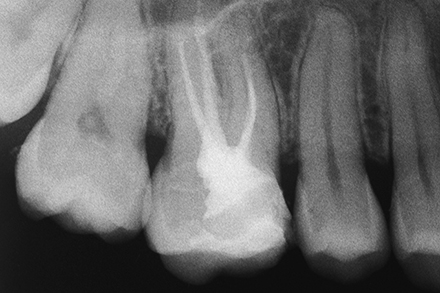

The image shows an insufficient RCT.

The MBII canal has been found, shaped and sealed up to the confluence with the MBI canal.